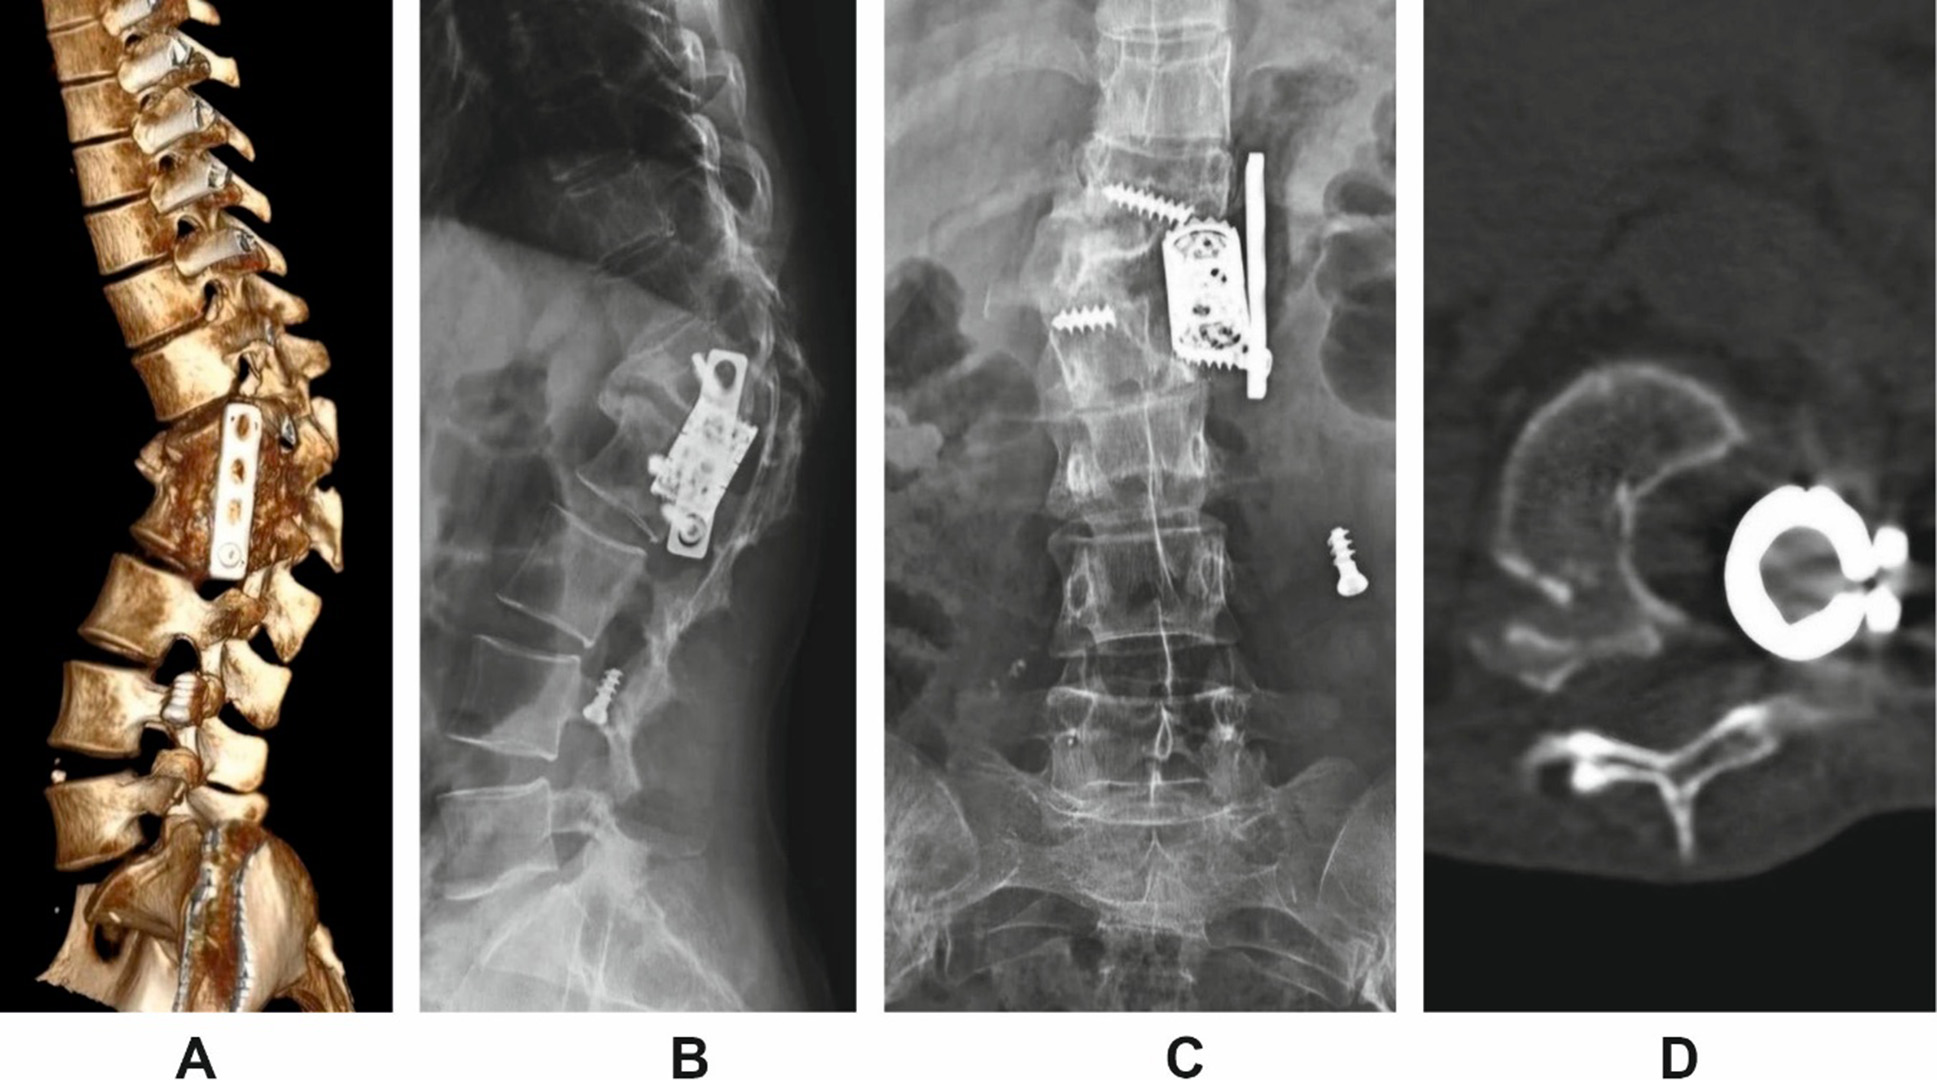

Clinical case 2

Patient H. underwent anterior stabilization of a thoracolumbar fracture at the age of 16 in 2009. Eleven years after the initial surgery, she presented with progressive spinal deformity and chronic lower back pain.

Radiographic and CT assessment revealed implant failure, anterior construct loosening, and severe kyphotic deformity. The measured Cobb angle was 69°, accompanied by global sagittal imbalance (increased SVA) and segmental instability (Fig. 2).

Fig. 2. Imaging findings in Patient H. prior to revision surgery.

A: 3D lateral reconstruction;

B: lateral scout view;

C: anteroposterior scout view;

D: axial view showing cage subsidence and anterior column failure.

The patient underwent revision surgery via a posterior-only approach. The procedure involved posterior instrumentation with pedicle screws, vertebral body resection, cage placement, and posterior column osteotomy for correction of the deformity. Anterior implants were not revised. Postoperative imaging confirmed restoration of sagittal alignment and segmental stability (Fig. 3).

Fig. 3. Postoperative imaging following posterior revision in Patient H.

A and B: 3D lateral reconstructions from left and right sides;

C and D: scout views (anteroposterior and lateral);

E: midsagittal CT reconstruction demonstrating correction of segmental alignment.